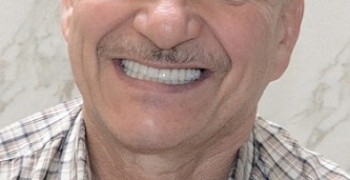

21 работа в портфолио